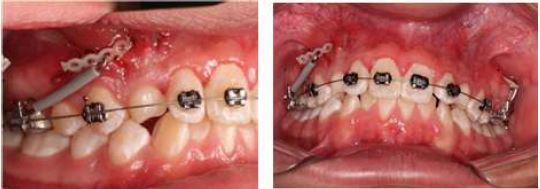

During the first orthodontic controls, brackets were not attached to manage the free-body concept and avoid greater effects in the root zone of 21 and 22. Tooth 63 was not extracted because it was not the time for its exfoliation and due the position of 23. A 60 g force was applied to 23 with a distal traction vector anchored by an infrazygomatic mini-implant.

A distal traction vector of tooth 23 continued for 5 months with monthly activations with a force of 60 g. In May 2019, in the radiographic control, the crown of 23 was further away from tooth 21 but still in contact with tooth 22, for which the distal traction of tooth 23 continued for another 4 months. Additionally, it was decided to perform bimaxillary orthodontic adhesion with a 0.022-inch Roth sloth prescription, due to the patients’ aesthetic requirements. Brackets were bonded to 22 and 63, but 22 was not tied to the arch due to its proximity to 23. The patient underwent surgery again to change the force vector in the disto-occlusal direction (Figure 4).

Follow-up Images, Case 1

FIGURE 4

Tooth 23 radiographically and with replacement of the direct cementation button with the new traction vector. Source: the authors with permission from the patient.

After the second surgical procedure, the traction of tooth 23 continued with a disto-occlusal vector using a 0.017” x 0.025” cantilever in TMA, without extracting 63 and removing the brackets of 24 and 25 using the segmented arch concept (11). It was adapted from the tube on 26, using the infrazygomatic mini-implant as indirect anchorage. In the control radiograph (Figure 4) a greater resorption of the apical third of tooth 22 was observed, continuing radiographic controls and maintaining tooth 22 without ligation using the free-body concept. The vitality tests did not show alterations in said tooth.

Two months later, the team decided to extract 63 and continue with cantilever disto-occlusal traction. It is relevant to note that, due to the pandemic generated by COVID-19, the patient did not have orthodontic controls for 5 months. In the next control tooth 23 showed a more occlusal position but insufficient space. In addition, 22 had a stable root length. The brackets were adhered to 24 and 25 and remained passive to preserve the root position and the distalization mechanics began in quadrant II of 24 with anchorage to the mini-implant. Once obtained sufficient space for tooth 23, occlusal traction of said tooth continued with nickel-titanium overarches and elastic thread. Once obtained a better position of 23, the respective bracket was adapted and its alignment and proper positioning in the arch continued (Figure 5).

During the surgery follow-up, MBT slot 0.022" x 0.028" brackets were attached to the upper arch, keeping the 12 and 22 brackets passive. The deciduous canines were kept in order to preserve the spaces and their extraction was scheduled when the path of eruption of the permanent canines was corrected. During the first controls, a distal traction force of 60 g was applied to both canines by activating the chain (Figure 9).

Activation of Chains on Teeth 13 and 23, Case 2

FIGURE 9

Source: the authors with permission from the patient.